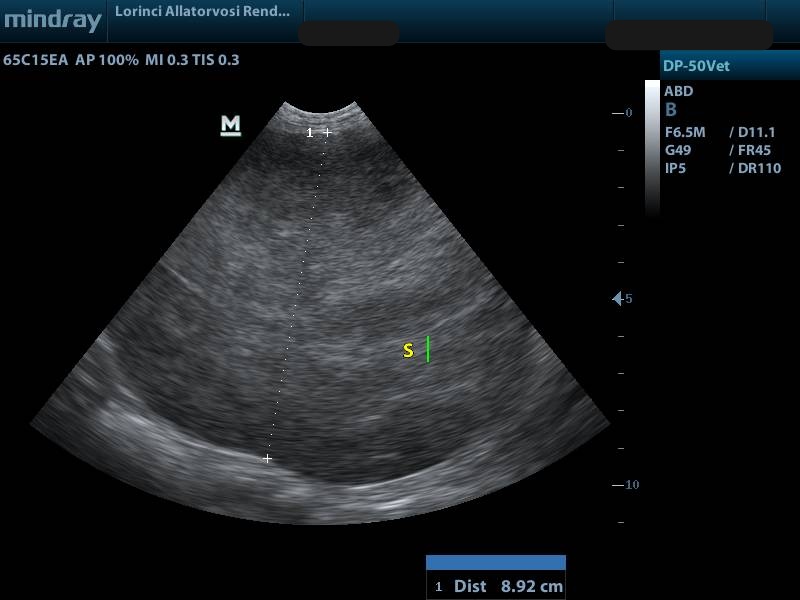

Megnagyobbodott lép hasi ultrahang felvétele

Megrepedt lépdaganat, következményes hasi folyadékgyülem

(képeken lévő rövidítések S: lép, L: máj, FAF: hasűri folyadék)